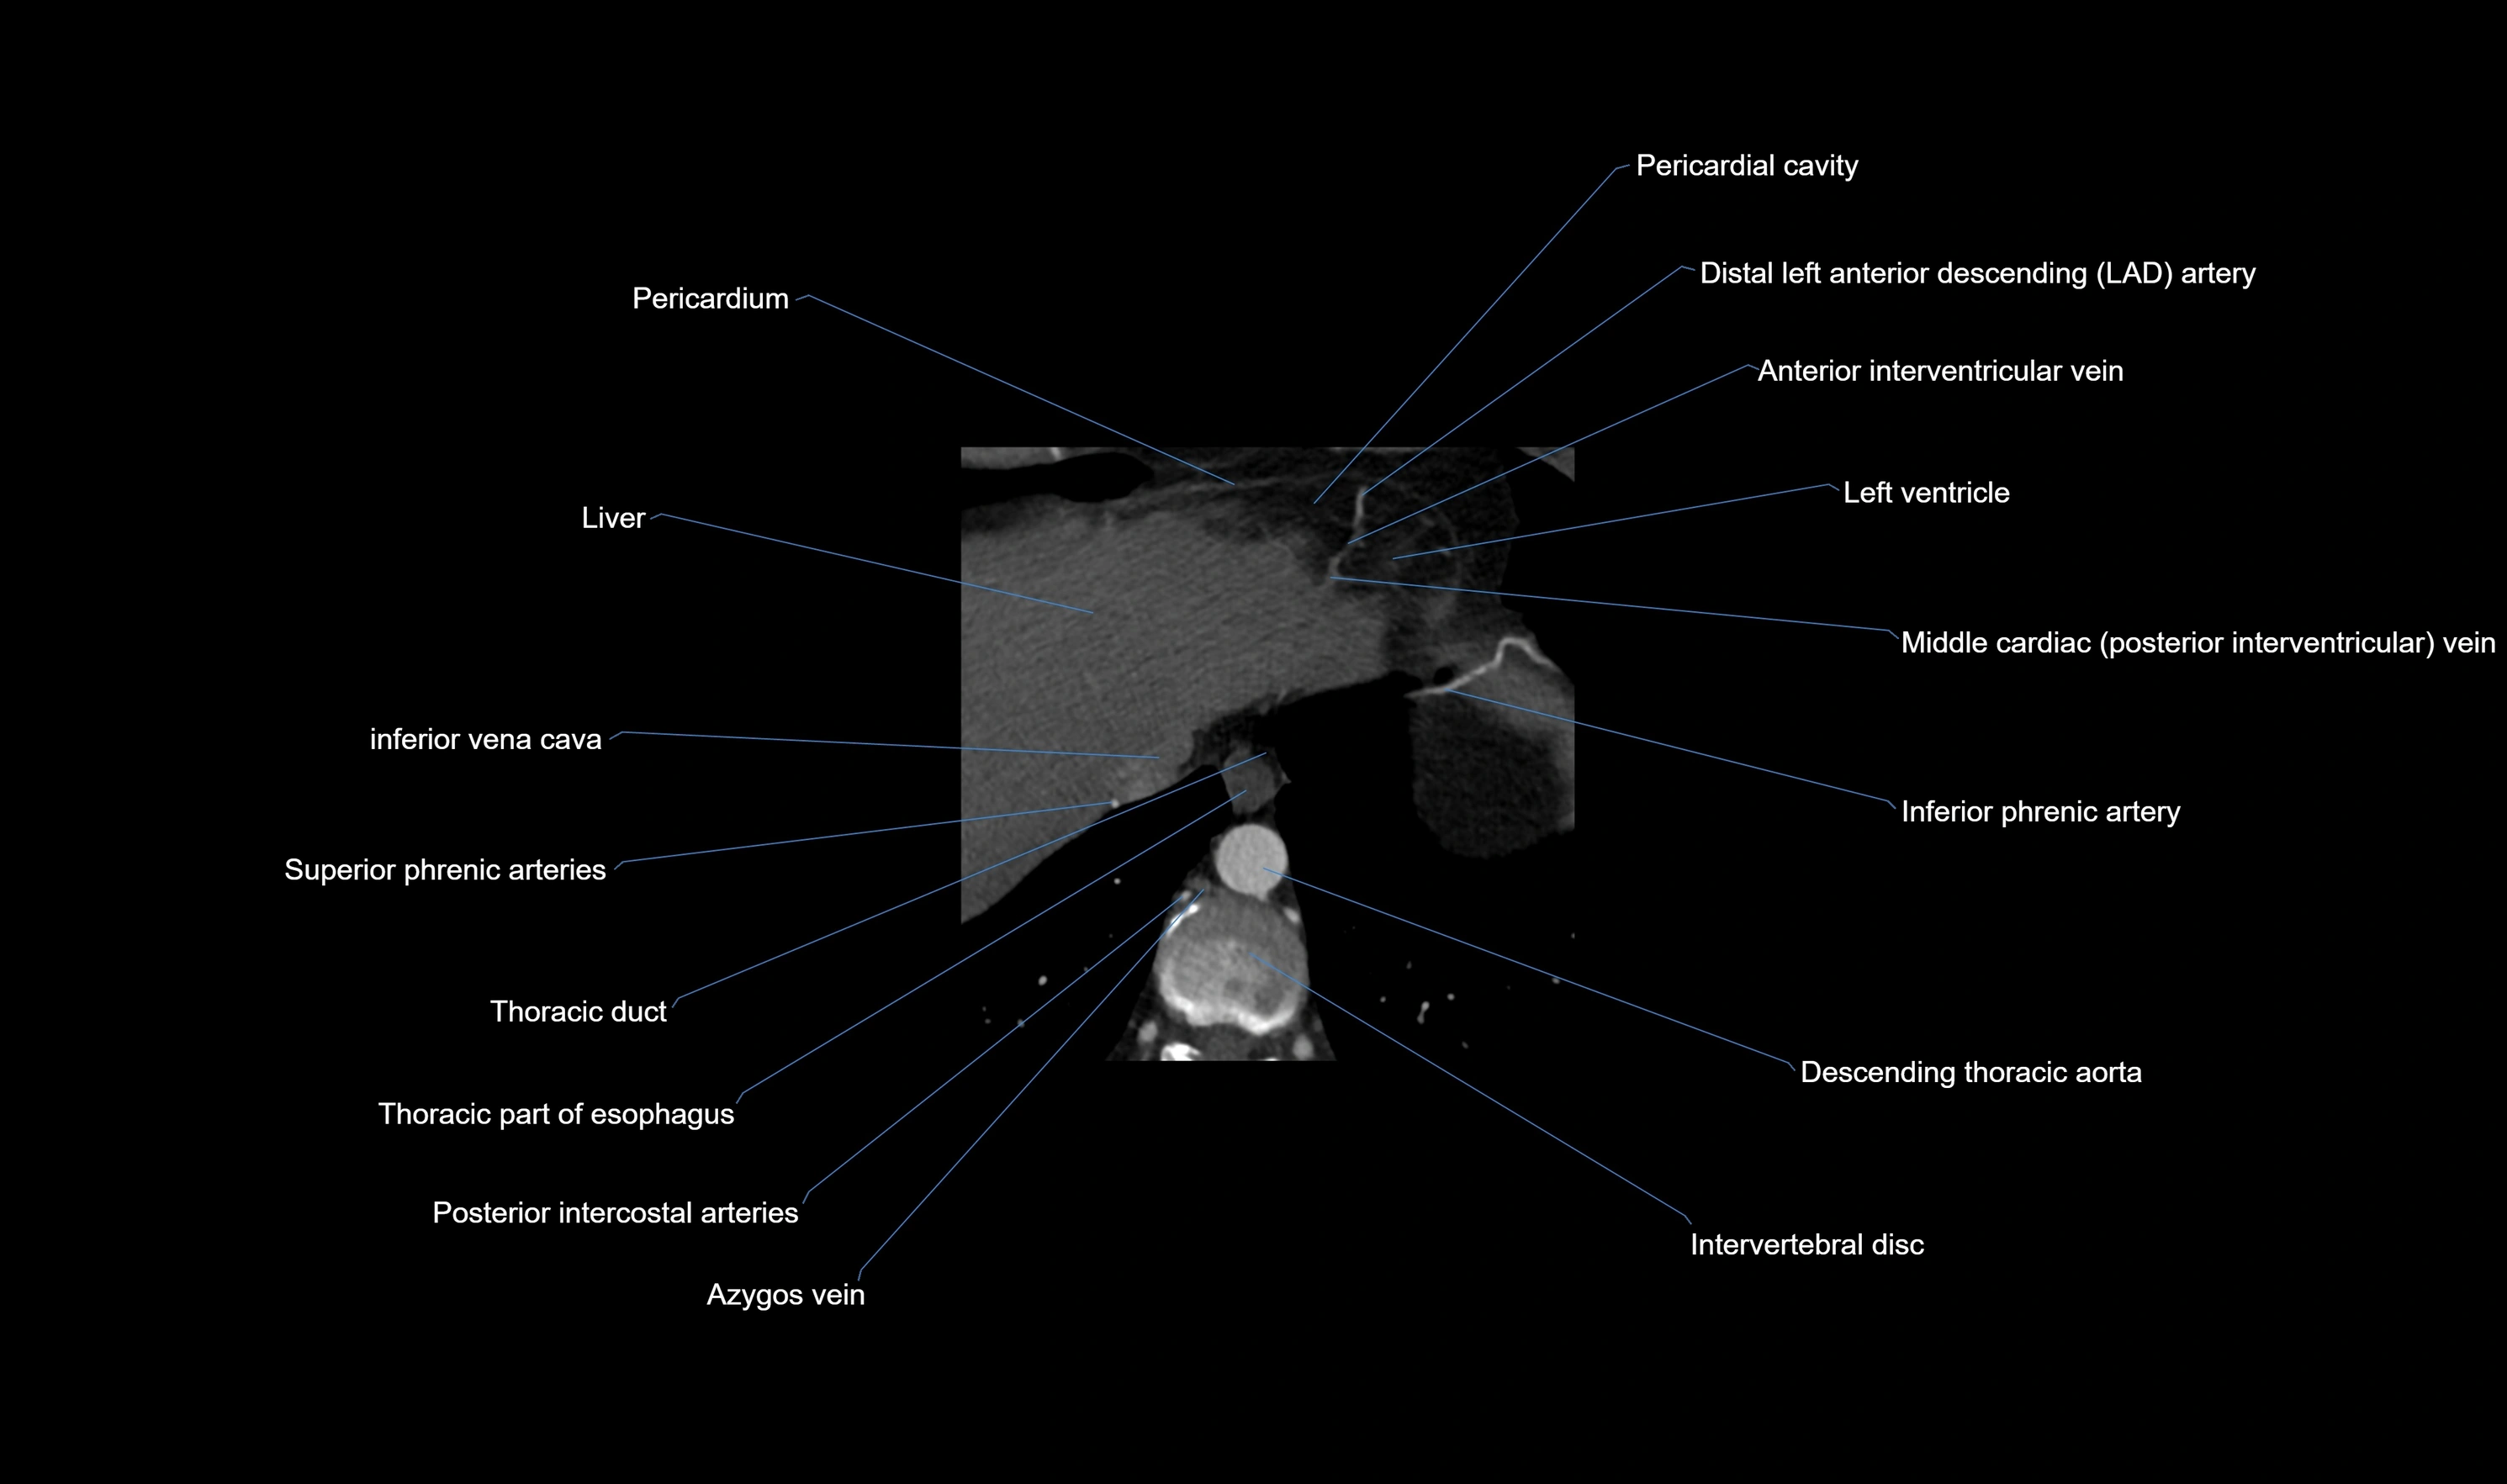

- Azygos vein

- Descending thoracic aorta

- Distal left anterior descending artery (dLAD)

- Inferior phrenic artery

- Inferior vena cava

- Left ventricle

- Middle cardiac vein

- Pericardial cavity

- Pericardium

- Posterior intercostal arteries

- Thoracic duct